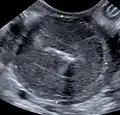

Größere solide Tumoren können unter Umständen bereits durch die Bauchwand ertastet werden. Weitere Hinweise können eine Sonografie, eine Endoskopie oder eine Bauchhöhleneröffnung geben. Die Diagnose wird wiederum durch Biopsie und Zytologie gestellt.